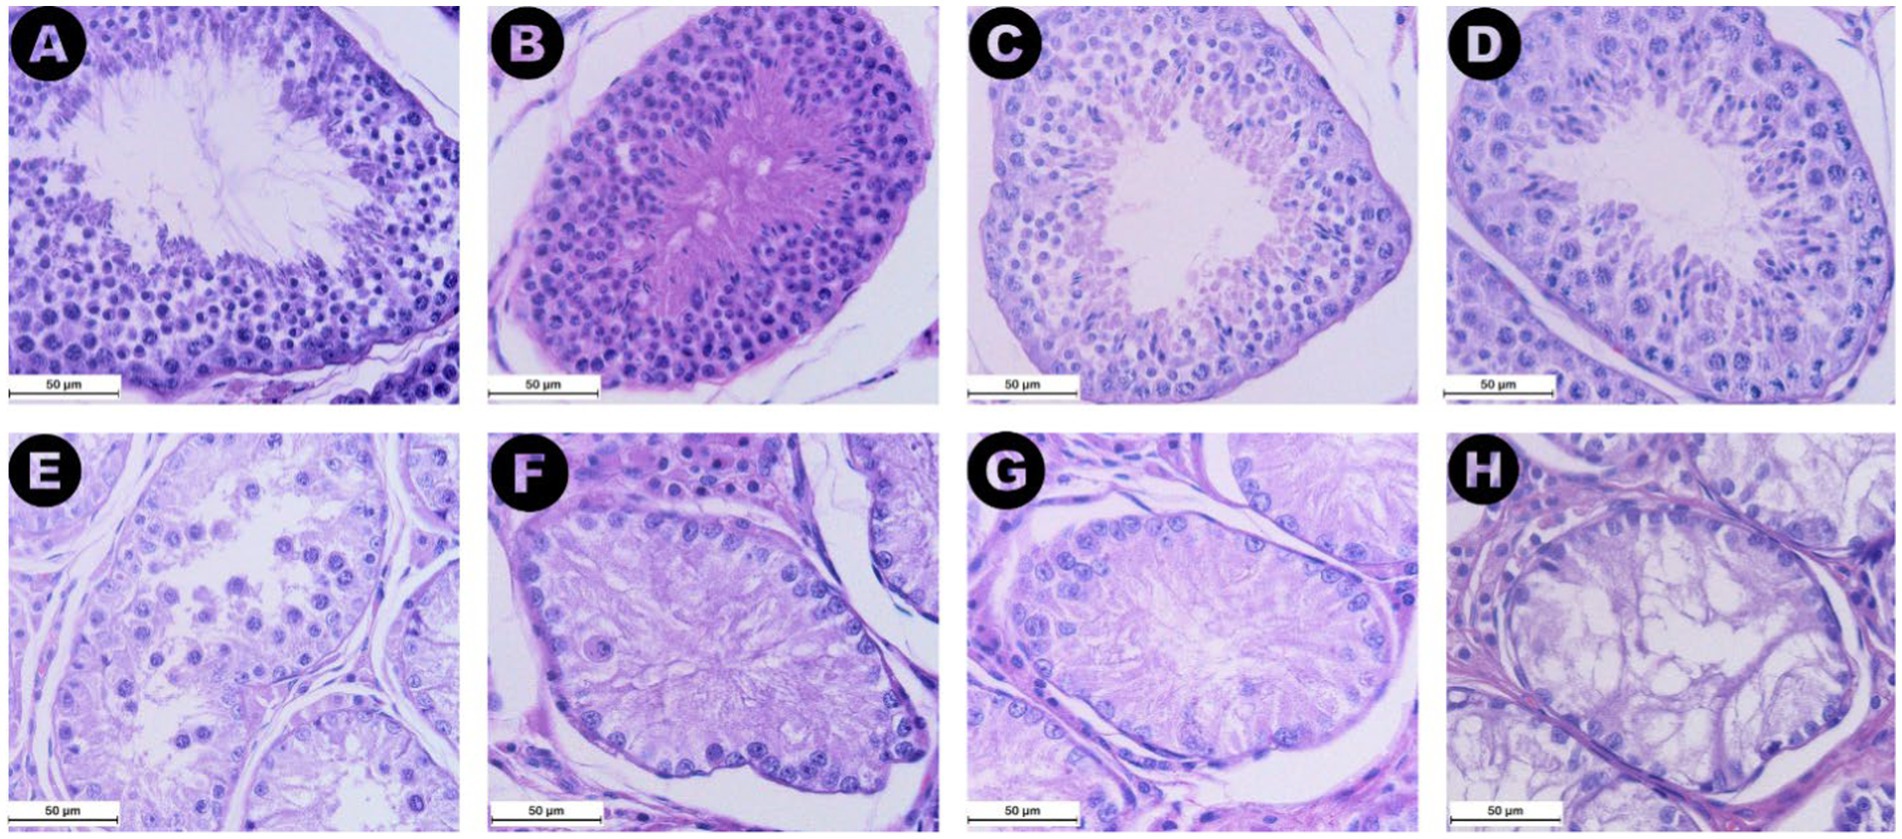

Utilizando los portaobjetos teñidos con HE, se analizaron 20 secciones de túbulos seminíferos y el compartimento intersticial vecino por muestra. Se evaluaron los rasgos histológicos generales específicos de la degeneración testicular, como la reducción del diámetro de los túbulos seminíferos, la disminución del número de células germinales y la fibrosis intersticial (27). Para la evaluación de la espermatogénesis, se evaluó la presencia de diferentes tipos de células dentro de los túbulos seminíferos: espermatogonias, espermatocitos, espermátidos, espermatozoides y células de Sertoli. A partir de esta evaluación, se asignó una puntuación del 1 al 10 a cada una de las 20 secciones, siguiendo los criterios de la escala de Johnsen adaptada para su uso en perros (28).

3.2.3 Puntuación de Johnsen

Todos los valores de la puntuación de la escala de Johnsen se han asignado a las secciones de las tres categorías, excepto las puntuaciones 1 y 6 (Figura 6). La puntuación de Johnsen para la categoría RET (mediana 2, IQR = 0,5) fue significativamente menor que la de los grupos CONTRA (mediana 9,2, IQR = 0,8, p ≤ 0,05) y DES (mediana 9,7, IQR = 0,4, p ≤ 0,001) (Figura 5B). Además, las puntuaciones más altas se asociaron con niveles séricos de AMH más bajos (ρ = −0,537, p ≤ 0,01) y túbulos seminíferos más grandes (ρ = 0,828, p ≤ 0,001). Al igual que en las áreas de túbulos seminíferos, la comparación entre la distribución de las puntuaciones de Johnsen asignadas a las gónadas inguinales y abdominales no mostró diferencias significativas (p = 1,000).